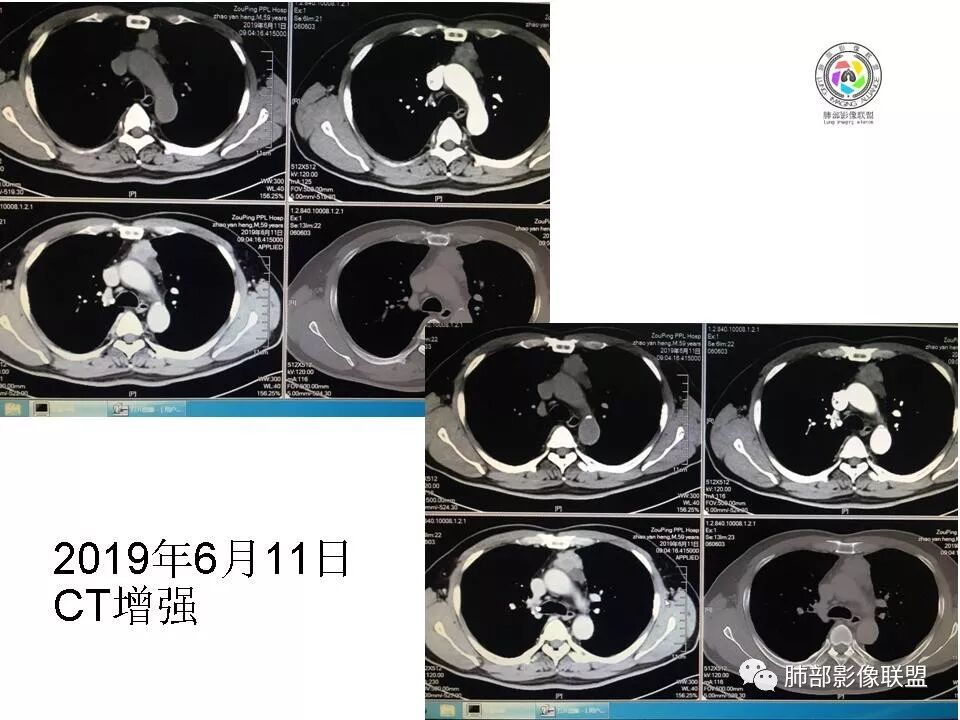

胸腺瘤(B2–C)型。中年男性,体检前上纵隔近奇静脉水平不规则呈生姜样占位,密度不均,延迟强化,进行性增大。

胸腺区实性占位,呈分叶状,病灶近一年间明显增大,增强扫描中度强化,病灶与周围组织界限模糊,考虑恶性,胸腺癌(鳞癌)。

胸腺区占位,较前明显增大,病灶边缘不规整,病灶明显强化,考虑侵袭性胸腺瘤

胸腺区实性占位,呈分叶状,病灶近一年间明显增大,增强扫描中度强化,病灶与周围组织界限模糊,考虑恶性,没有胸水,胸腺癌可能。

男,59

2015年小,2019年增强,不规则强化不均匀。

48-60-70,28-30-24,不规则渐进性强化,密度不均。

诊断:侵袭性胸腺瘤